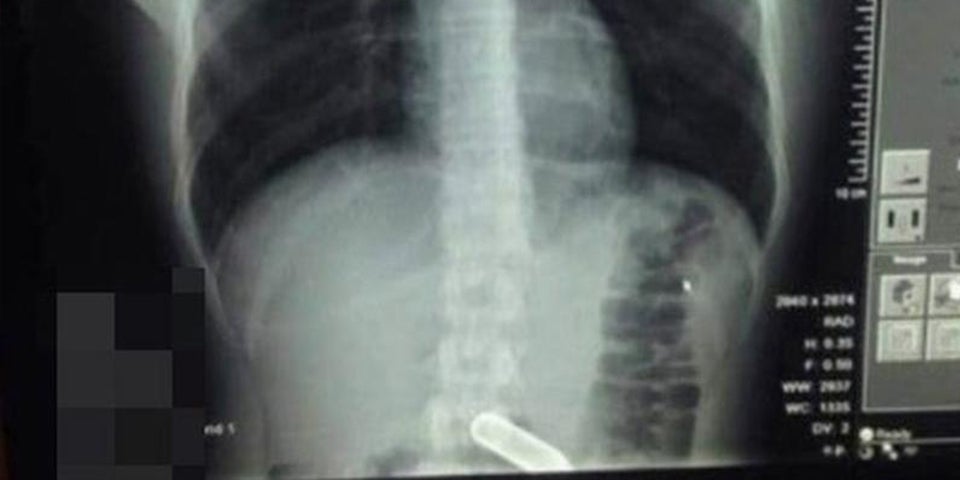

Mann schluckt Lachgas-Kapsel - Explosionsgefahr

Durch einen Notfall-Eingriff im Krankenhaus konnte die Kapsel entfernt werden. Wäre sie explodiert, hätte es den Mann von innen zerfetzt.

Es begann mit einer dummen Party-Wette: Ein 22-jähriger Brite bekam von seinen Freunden umgerechnet 55 Euro angeboten, wenn er eine Lachgas-Kapsel schlucken würde. Laut Ärzten war schon das Runterschlucken der Kapsel eine "anatomische Sensation".

Einer der nüchternen Partygäste schlug daraufhin Alarm und riet seinem Kumpel, in die Notaufnahme zu fahren - dort angekommen, wurde der junge Mann von staunenden und ratlosen Ärzten umringt, wie er im Interview mit dem Daily Mirror erzählt: „Als die Ärzte sich berieten, hatten sie Angst, dass die Kapsel explodieren könnte. Wenn das passiert wäre, dann wäre ich von innen zerfetzt worden.“

Doch die Experten schafften es, die Kapsel ganz ohne Operation zu entfernen - und zwar mit einem kleinen Netz durch den Darm.